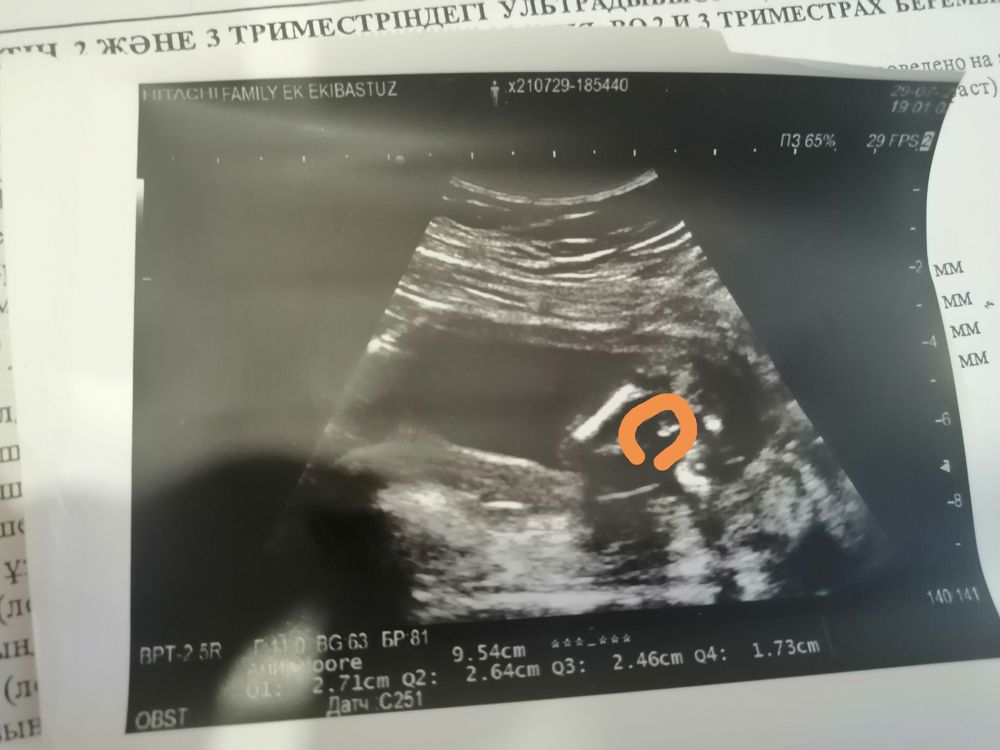

Мальчишка))) снимок попы и хозяйства)))

Ritik, да, а где Вы увидели? Объясните мне пожалуйста, вот здесь?! Изображение

Настя Литвинова, ну да, по бокам ножки, а между краник 😅